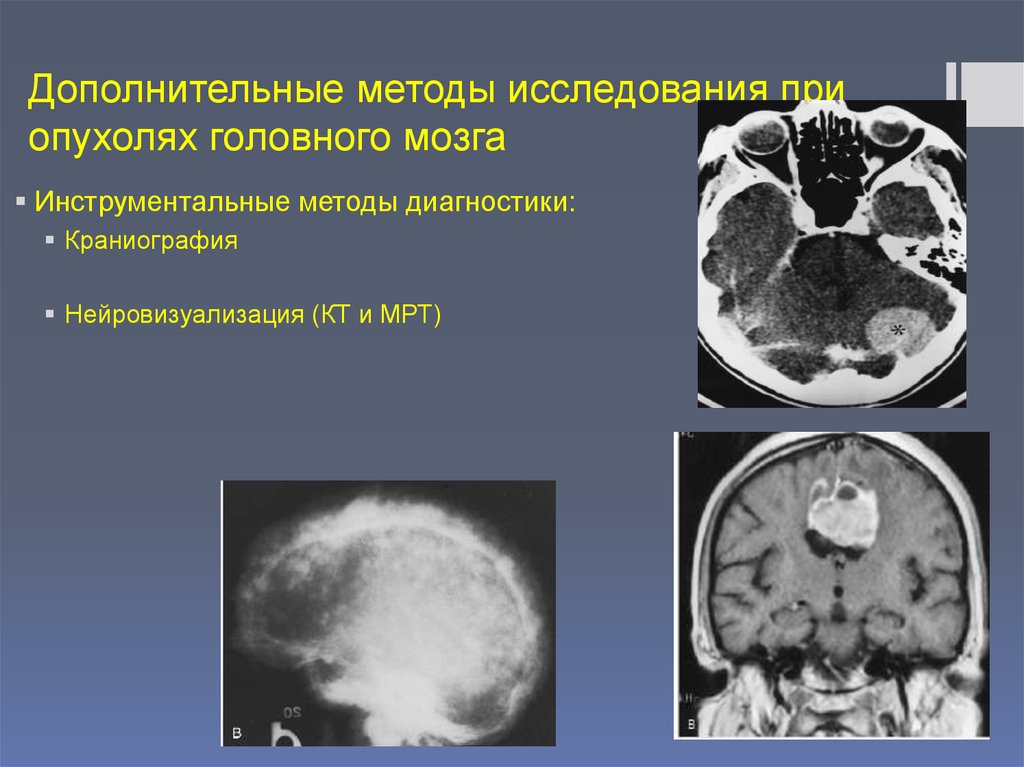

Опухоль головного мозга стадии. Опухоль головного мозга симптомы. Проявление опухоли головного мозга. Степени опухолей головного мозга. Методы исследования при опухоли головного мозга. Дополнительные методы исследования опухолей головного мозга. Диагноз кт с опухолью головного мозга. Дополнительные методы исследования при опухолях головного мозга.

Методы исследования при опухоли головного мозга. Дополнительные методы исследования опухолей головного мозга. Диагноз кт с опухолью головного мозга. Дополнительные методы исследования при опухолях головного мозга. Диагностика ра а желудка. РВК желудка дипгностика. Иагностика рада желудка. Методы диагностики в онкологии.